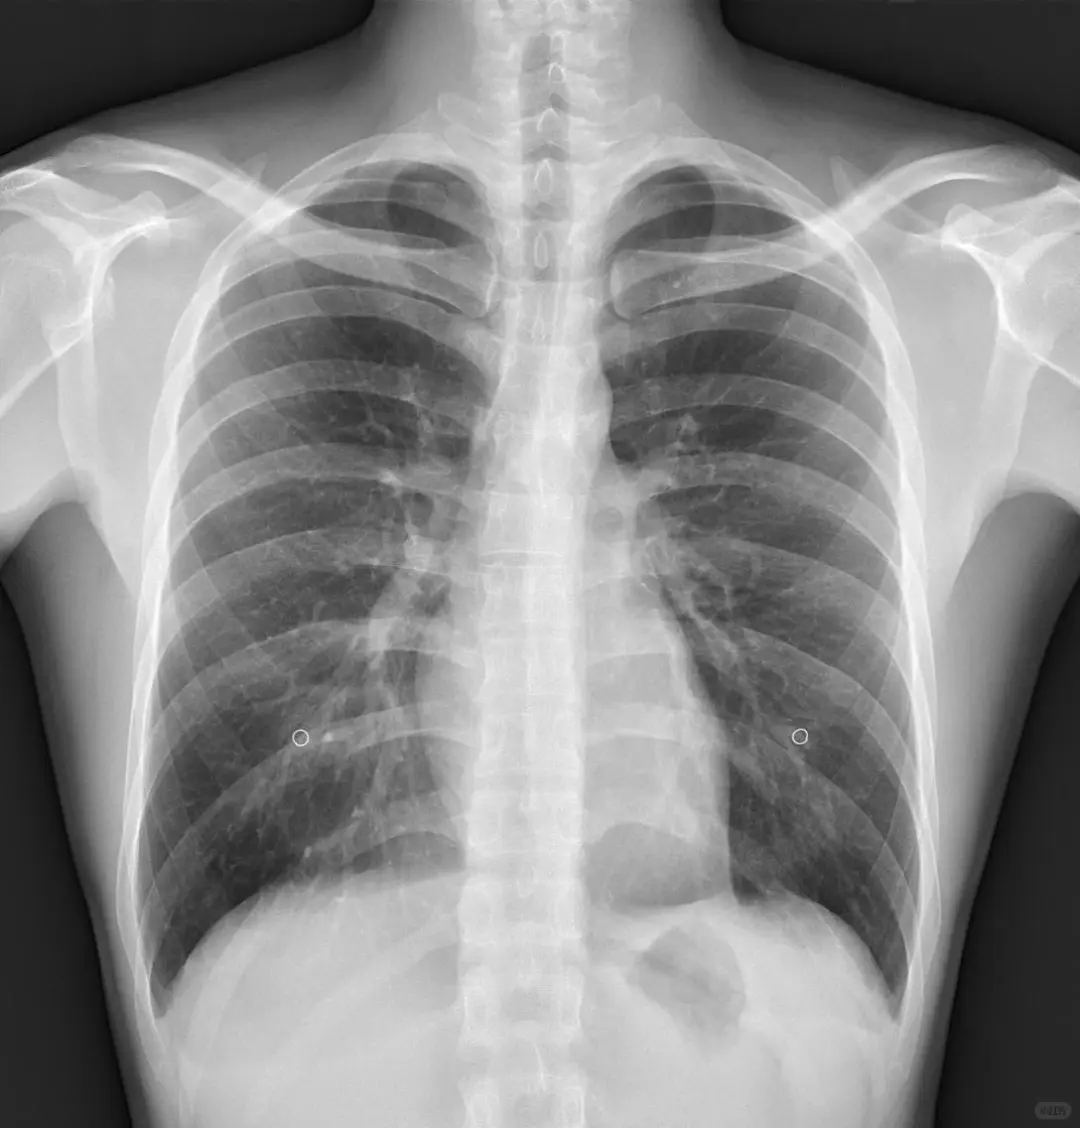

6. 胸部X光或肺部低剂量CT

筛查肺炎、肺结节、慢阻肺、早期肺癌等

吸烟人群强烈建议做肺部CT,比X光更精准。